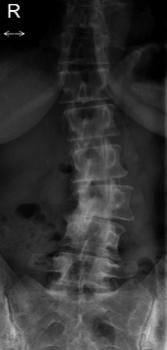

These are her back X-rays. You can see the scoliosis, and a severely degenerated lumbar joint at L3 - L4.

My initial impression was a severely pinched nerve in the low back. At L3/L4 the pain would radiate to the front of the leg. Plus the Femoral nerve stretch test was positive. This has in many ways the appearance of a lumbar stenosis, a chronic narrowing of the spinal canal.